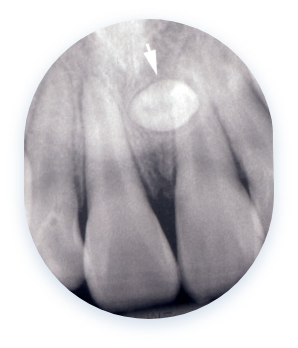

사랑니 물혹